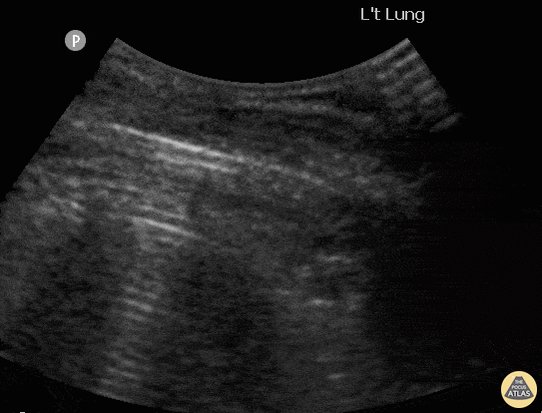

Prenatal Ultrasonography Findings Of Fetus With Congenital High Airway Obstruction Chaos A Case Report And Review Of Literature